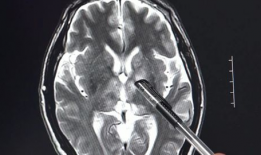

脑膜刺激征检查视频,直观解析临床诊断技巧

你有没有想过,去医院看病的时候,医生有时候会给你来点“特殊待遇”?比如说,给你做个脑膜刺激征检查。这听起来是不是有点陌生?别急,...